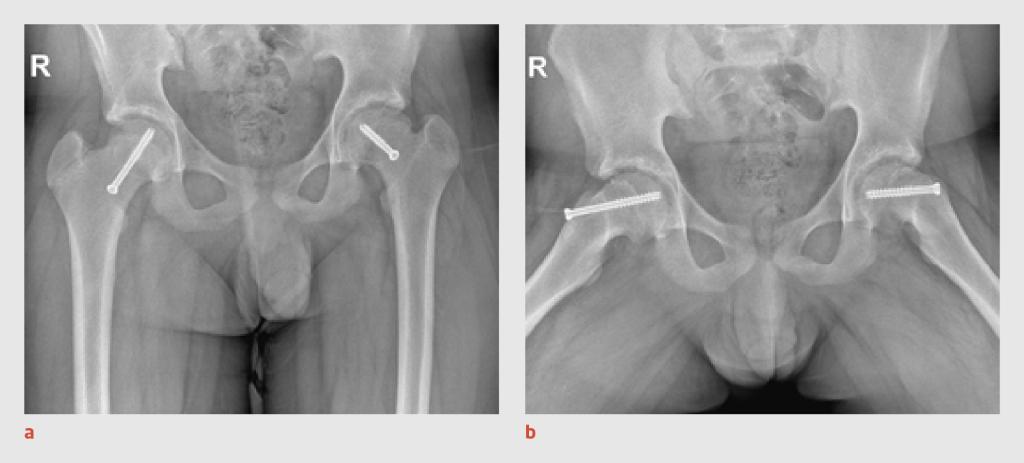

Figuur 3

Progressie en behandeling van de ziekte van Perthes

Figuur 3 | Progressie en behandeling van de ziekte van Perthes

Röntgenopnames van het bekken. (a) Ondanks ontlasten van de heup is een half jaar na de diagnose verdere afplatting en sclerose van het caput ossis femoris opgetreden. (b) Status 3 maanden na correctie-osteotomie van het linker proximale femur, waarbij de positie van het femur ten opzichte van het acetabulum is verbeterd.

Bij controle 3 maanden na de operatie liep patiënt zonder pijn en was op de controlefoto een geconsolideerde osteotomie te zien (zie figuur 3). Wij zullen de controles vervolgen totdat patiënt is uitgegroeid.